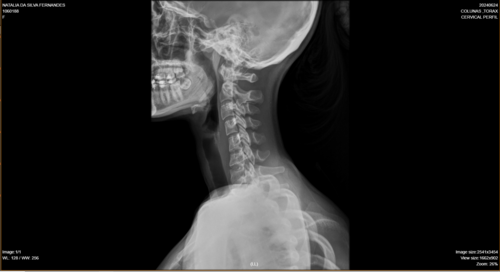

Olá, me chamo Natália da Silva Fernandes, tenho 21 anos, moro na cidade de Ji-Paraná, no estado de Rondônia. Fui diagnosticada com escoliose e venho na busca de um tratamento pelo SUS há um tempo, mas não obtive retorno até o presente momento. Passei por algumas consultas com ortopedistas do SUS, peguei encaminhamentos para passar com um neorocirurgiao e depois de um longo período de espera, consegui uma consulta com um neorocirurgiao do SUS, quando ele viu meu estado de saúde ele disse q a única solução é fazer a cirurgia, como na cidade não tem estrutura para realizar a cirurgia através do SUS, peguei mais um encaminhamento para consultar pela segunda vez por outro neurocirugiao, mas na cidade de Porto Velho, e nisso fiquei no aguardo desse agendamento mas até o momento nenhum retorno do SUS, ou seja, nenhum pedido de agendamento de cirurgia, apenas consultas, é um processo burocrático conseguir uma cirurgia pelo SUS, pois tem uma lista de pacientes na espera por vaga. Devido à demora do SUS , recorri a um neurocirurgião particular e o diagnóstico que recebi foi o mesmo, necessito fazer a cirurgia com urgência.Atualmente, me encontro num quadro doloroso, minha escoliose está com 86° de encurvatura, sinto dores constantes, tenho dificuldade em andar e às vezes dificuldade em respirar, porque são dores muito fortes. Para dormir, é uma luta constante para achar uma posição que dê menos desconforto . Diante de todo esse processo doloroso, e todo o tempo que venho recorrendo ao SUS e não obtendo uma solução favorável, a preocupação aumenta cada dia, pois não tenho condições de custear nem a cirurgia, nem o tratamento pós-cirúrgico. Foi então que surgiu a solução de fazer a vaquinha. A cirurgia fica em média de 250 mil reais com o tratamento pós-cirúrgico. Deixo na descrição os laudos e exames que venho realizando como transparência da minha situação.Toda ajuda é bem-vinda!Ajude-me compartilhando em suas redes sociais. Deixarei minha rede social para entrarem em contato comigo para mais informações: @_fe3_n47ou acesse o link abaixo e vá direto ao meu perfil.https://www.instagram.com/_fe3_n47?igsh=MXA1bDEzNW53YzZ5NA==